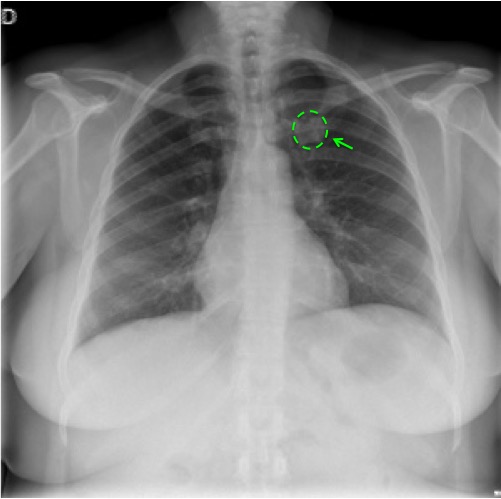

CASO: Febrícula y tos de 4 días de evolución.

Hallazgos:

- En la placa PA se observa una asimetría en los hilios pulmonares, el hilio izquierdo tiene una densidad aumentada.

- Tras examinar la placa lateral se observa un aumento de densidad en la columna que puede ser compatible con una condensación, es el signo de la desnificación vertebral.

SIGNO DE LA DENSIFICACIÓN VERTEBRAL: En la radiografía lateral normal, la densidad de la columna torácica tiende a disminuir desde la parte superior hasta el diafragma; la alteración de ese patrón por la presencia de una densidad superpuesta a la columna, indica la existencia de una consolidación pulmonar. Este signo adquiere especial valor cuando en la proyección posteroanterior la consolidación está oculta en el espacio retrocardíaco o en la base pulmonar.